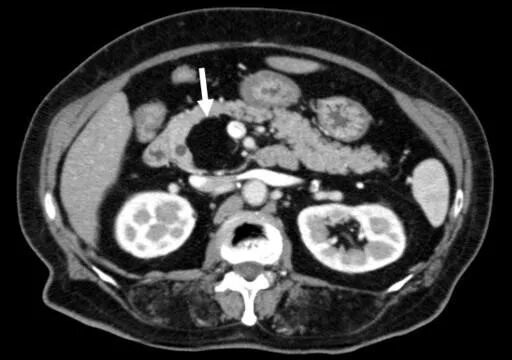

Диффузные изменения печени липоматоза